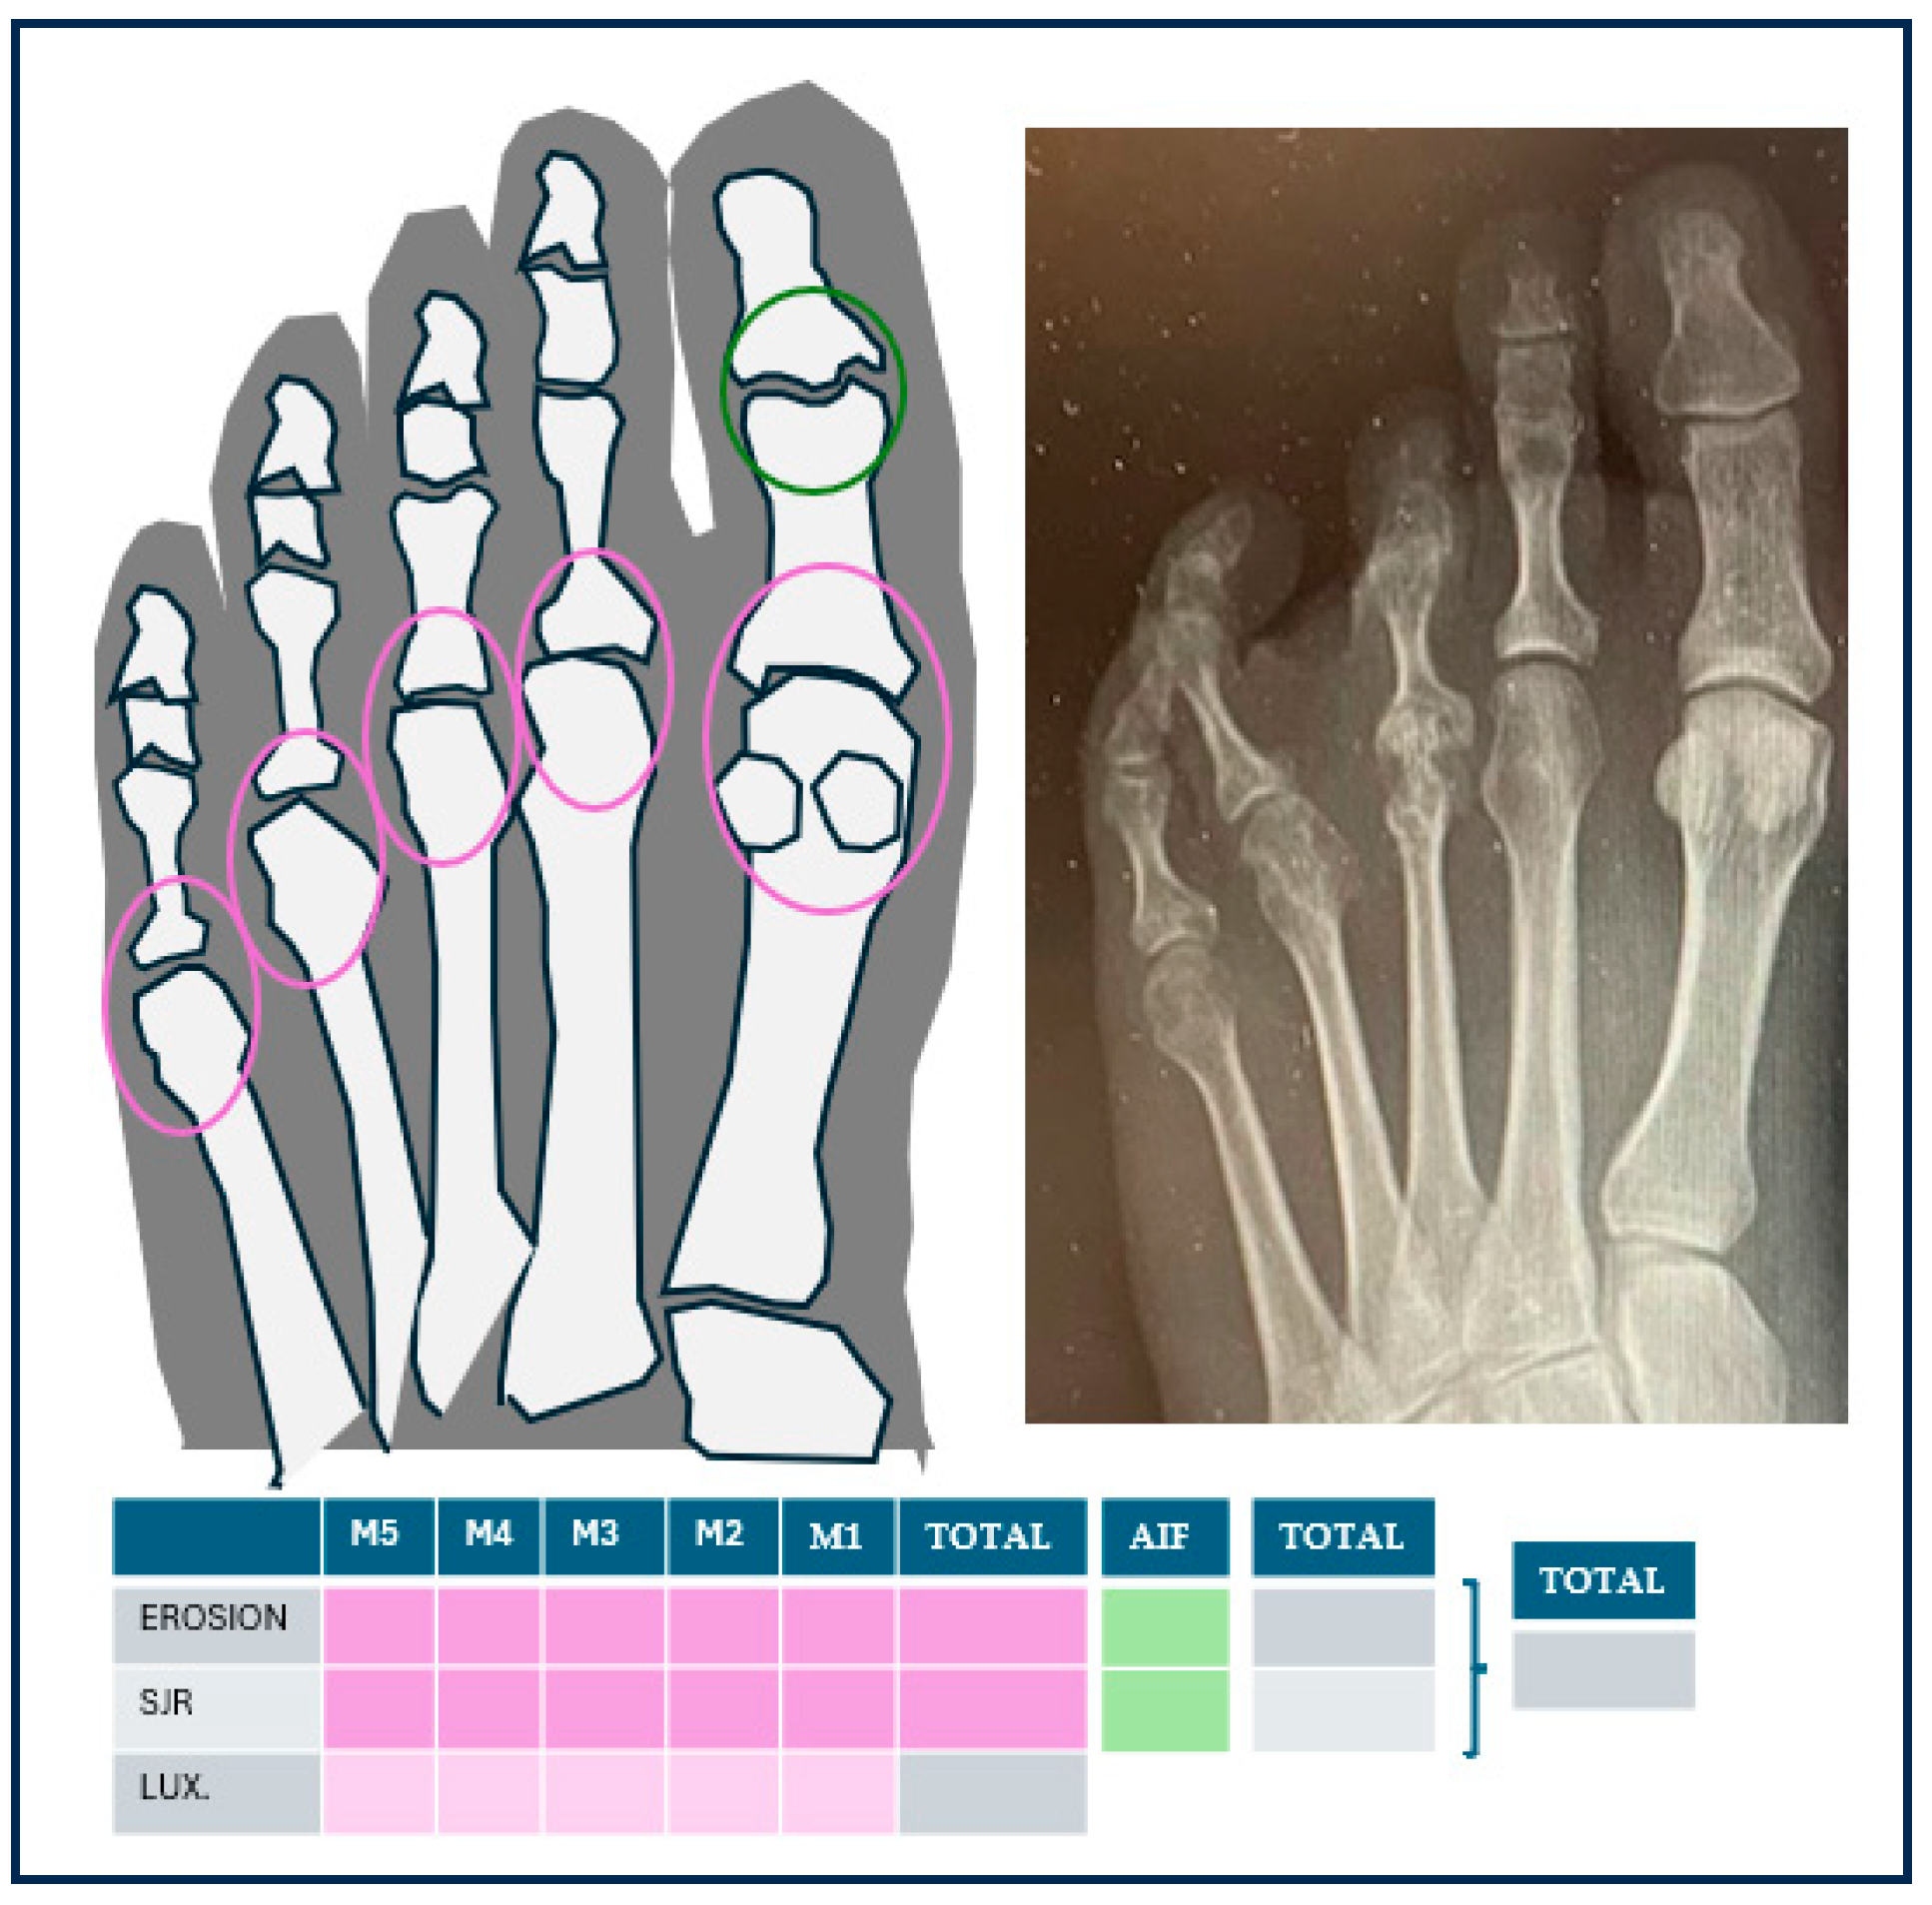

| Radiology | mRA (n = 84) | nmRA (n = 60) | ||||

|---|---|---|---|---|---|---|

| JSR affectation | Mean | sd | Mean | sd | p | ICC 95% |

| 1st to 5th MTPJ * + IPJ hallux ** | 3.63 | 2.1 | 1.5 | 1.4 | 0.000 | (−2.59/−1.42) |

| 2nd to 5th MTPJ * | 2.439 | 1.7 | 0.7 | 1.2 | 0.000 | (−2.07/−1.06) |

| nº MTPJ * affected 2nd to 5th JSR *** | n patients | % | n patients | % | ||

| 0 | 20 | 23.8% | 36 | 60% | ||

| 1 | 12 | 14.3% | 9 | 15% | ||

| 2 | 4 | 4.7% | 8 | 13.3% | ||

| 3 | 4 | 4.7% | 1 | 1.6% | ||

| 4 | 42 | 50% | 4 | 6.6% | ||

| Affectation erosions | mRA | nmRA | ||||

| Mean | sd | Mean | sd | p | ||

| 1st to 5th MTPJ * + IPJ hallux ** | 2.5 | 1.7 | 0.1 | 0.3 | 0.000 | (−2.87/−2.10) |

| 2nd to 5th MTPJ | 1.9 | 1.4 | 0.1 | 0.3 | 0.000 | (−2.19/−1.56) |

| nº erosions 2nd to 5th MTPJ * | n patients | % | n patients | % | ||

| 0 | 13 | 15.5% | 52 | 86% | ||

| 1 | 24 | 28.6% | 5 | 8.33% | ||

| 2 | 17 | 20.2% | 0 | 0 | ||

| 3 | 11 | 13.1% | 0 | 0 | ||

| 4 | 18 | 21.4% | 0 | 0 | ||

| SENS scale total. JSR *** + erosions | 6.1 | 3.2 | 1.6 | 1.3 | 0.000 | (−2.87/−2.10) |

| Luxations or subluxations 2nd to 5th MTPJ * | Mean | sd | Mean | sd | p | |

| Subluxations/luxations 2nd to 5th | 2.0 | 1.6 | 0.7 | 1.1 | 0.000 | (−1.76/−0.84) |

| nº MTPJ * affected 2nd to 5th subluxations/luxations | n patients | % | n patients | % | ||

| 0 | 23 | 27.4 | 36 | 60 | ||

| 1 | 14 | 16.6 | 13 | 21.6 | ||

| 2 | 10 | 11.9 | 6 | 10 | ||

| 3 | 8 | 9.5 | 2 | 3.3 | ||

| 4 | 27 | 32.1 | 3 | 5 | ||